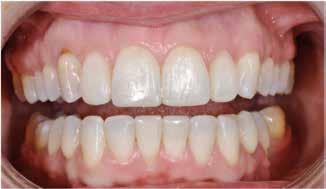

I samråd med patienten og egen tandlæge* afstemmes forventningerne, inden der bestilles refinement alignere. Nivelleringen af alle tænder i tandbuerne, smilelinje og -kurve samt den bukko-lingvale position af incisiverne foretages og efterfølges af retainers lingvalt på over- og underkæbeincisiver (Fig. 3 A-D). Hele behandlingen udføres under løbende kommunikation med patient og egen tandlæge*, der udfører den efterfølgende rekonstruktion med direkte plast (Fig. 4 A-D). Behandlingsvarigheden har været to år og to måneder, hvor ortodontien har forløbet over 21 måneder. Der har været anvendt et første sæt på 66 alignere samt yderligere to sæt med ni refinement alignere. Tandblegning og direkte plastrekonstruktion er udført af egen tandlæge* (Fig. 5 A-F).

Fig. 5. A, B. Smil og kæbeforhold før og efter. Et bredere smil med korrektion af de laterale mørke rum. C-F. Harmonisk hældning af overkæbe- og underkæbeincisiver, rekonstruktion af den tabte tandsubstans efter nivellering af gingivaniveau og optimal bukko-lingval placering til direkte plastbehandling.

5. A, B. Smile and jaw relationships before and after. A wider smile with correction of the lateral dark spaces. C-F. Harmonious inclination of the upper and lower jaw incisors, reconstruction of the lost tooth substance after leveling the gingival level, and optimal bucco-lingual positioning for direct plastic treatment.